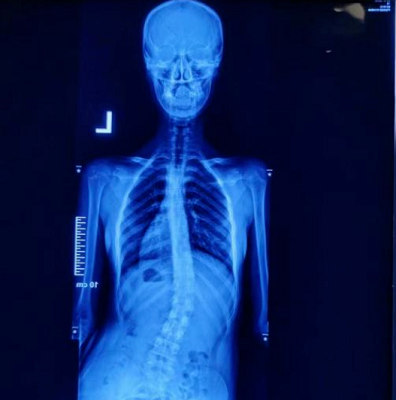

在站姿下,不管從正面或背面看,正常的脊椎排列應該是身體左右兩邊對稱,并且正常的脊椎排列從上到下是呈一直線的。

如果在站姿下看到脊椎向身體的任何一邊彎曲歪斜,就是有可能是脊椎側彎,左右手臂與軀干之間的空隙不對稱,右側肩膀較高。

然而大部分的脊椎側彎并不只有單一平面的左右傾斜,通常會伴隨著脊椎旋轉,往往也會影響到肩胛骨的動作,導致肩關節的活動度受限。

小櫻今年十三歲,剛上初二沒多久。兩個月前出現腰痛、胸悶氣短、會陰區不適、不思飲食等癥狀,而且由于體態不好,受到了一些同學的嘲笑,致使孩子脾氣變得很差,跟父母的關系也出現了很大的嫌隙。父母帶著去了一家醫院拍攝了X光片,診斷為脊柱側凸畸形。上家醫院給出的治療方案是直接手術,但了解到脊柱側彎手術會留疤,而且進行手術后還有復發或者其他并發癥風險,孩子十分排斥。后經多方打聽,來我院進行治療。

直樂醫院通過分析孩子的脊柱X光片,又對孩子進行了足底壓力、步態及肌力檢測,給出了一套以平衡正脊保守治療方式為主、運動矯形為輔的綜合治療方案對患者進行治療。按療程進行治療后,患者腰痛、胸悶氣短等癥狀有了較大的改善,心態也平和了許多,身體逐漸恢復的過程中,與父母、同學的關系也有了很大改善。